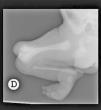

A nivel de extremidades inferiores, se constató la presencia de anomalía severa de la porción distal del fémur derecho «bífido» (ver fig. 2) y presencia de un solo hueso de la pierna, que no se identificó adecuadamente si correspondía a tibia o peroné. Además, presentaba anomalía y alteración de la alineación severa de los huesos del pie derecho.